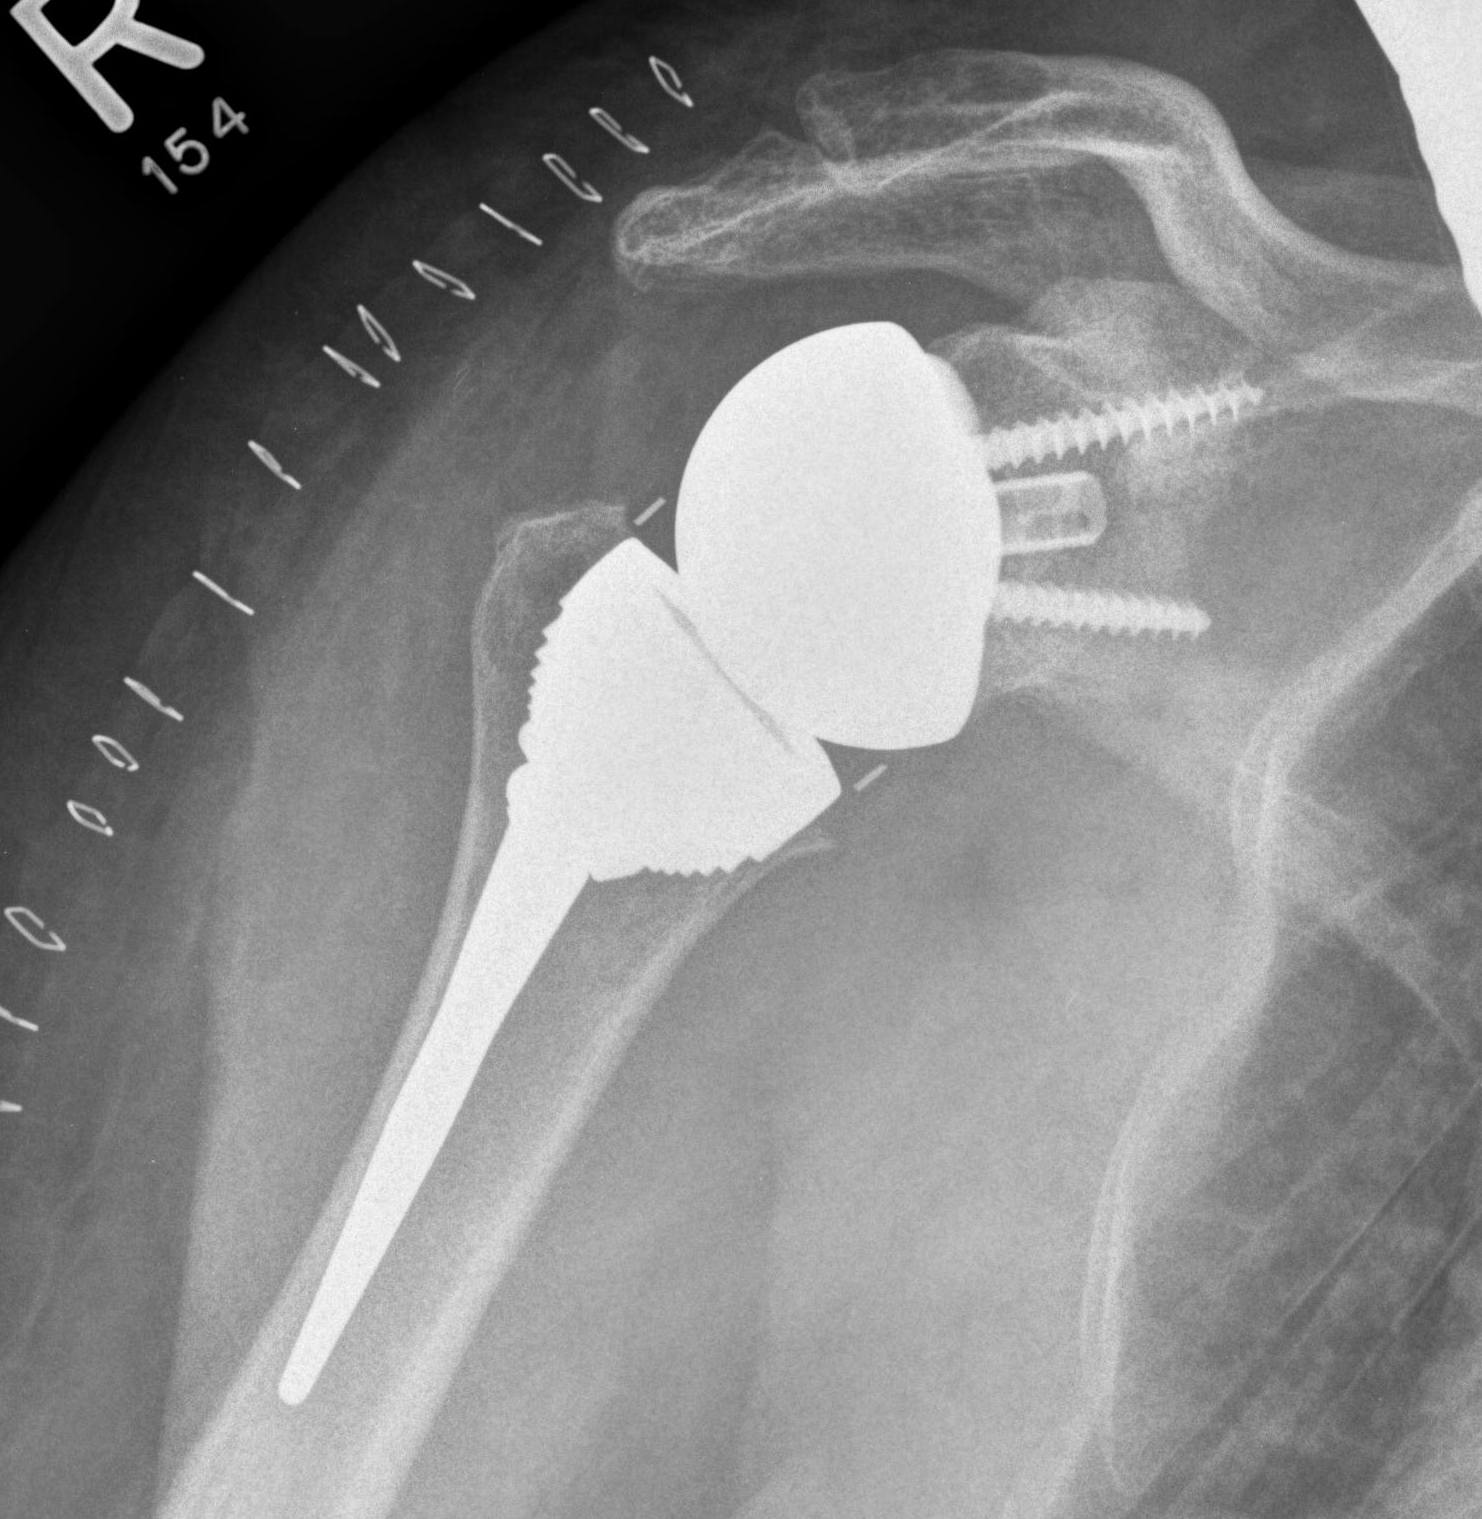

Reverse shoulder arthroplasty

Reverse

- socket in proximal humerus

- ball in glenoid

- center of rotation shifted medially and distally

- allows deltoid to apply compressive force and stabilize joint in absence of rotator cuff

Glenoid component

Metaglene / baseplate

Depuy Synthes Delta Xtend

Design

- uncemented

- coated central peg

- secured by compression non locking screws + locking screw

- +/- variable angle to allow inferior screws along scapular spine / superior screw into coracoid

Glenosphere

Press fit / morse taper onto baseplate

Lateralized / thicker options - limit scapular notching

Eccentric options - shift center of rotation inferior, limiting scapular notching

Humeral component

Fixation

Stem length

| Short <100mm (n=10,000) | 2.0 | 3.3 | 4.3 | 5.7 |

| Conventional > 100mm (n=13,500) | 1.8 | 3.6 | 5.4 | 7.3 |